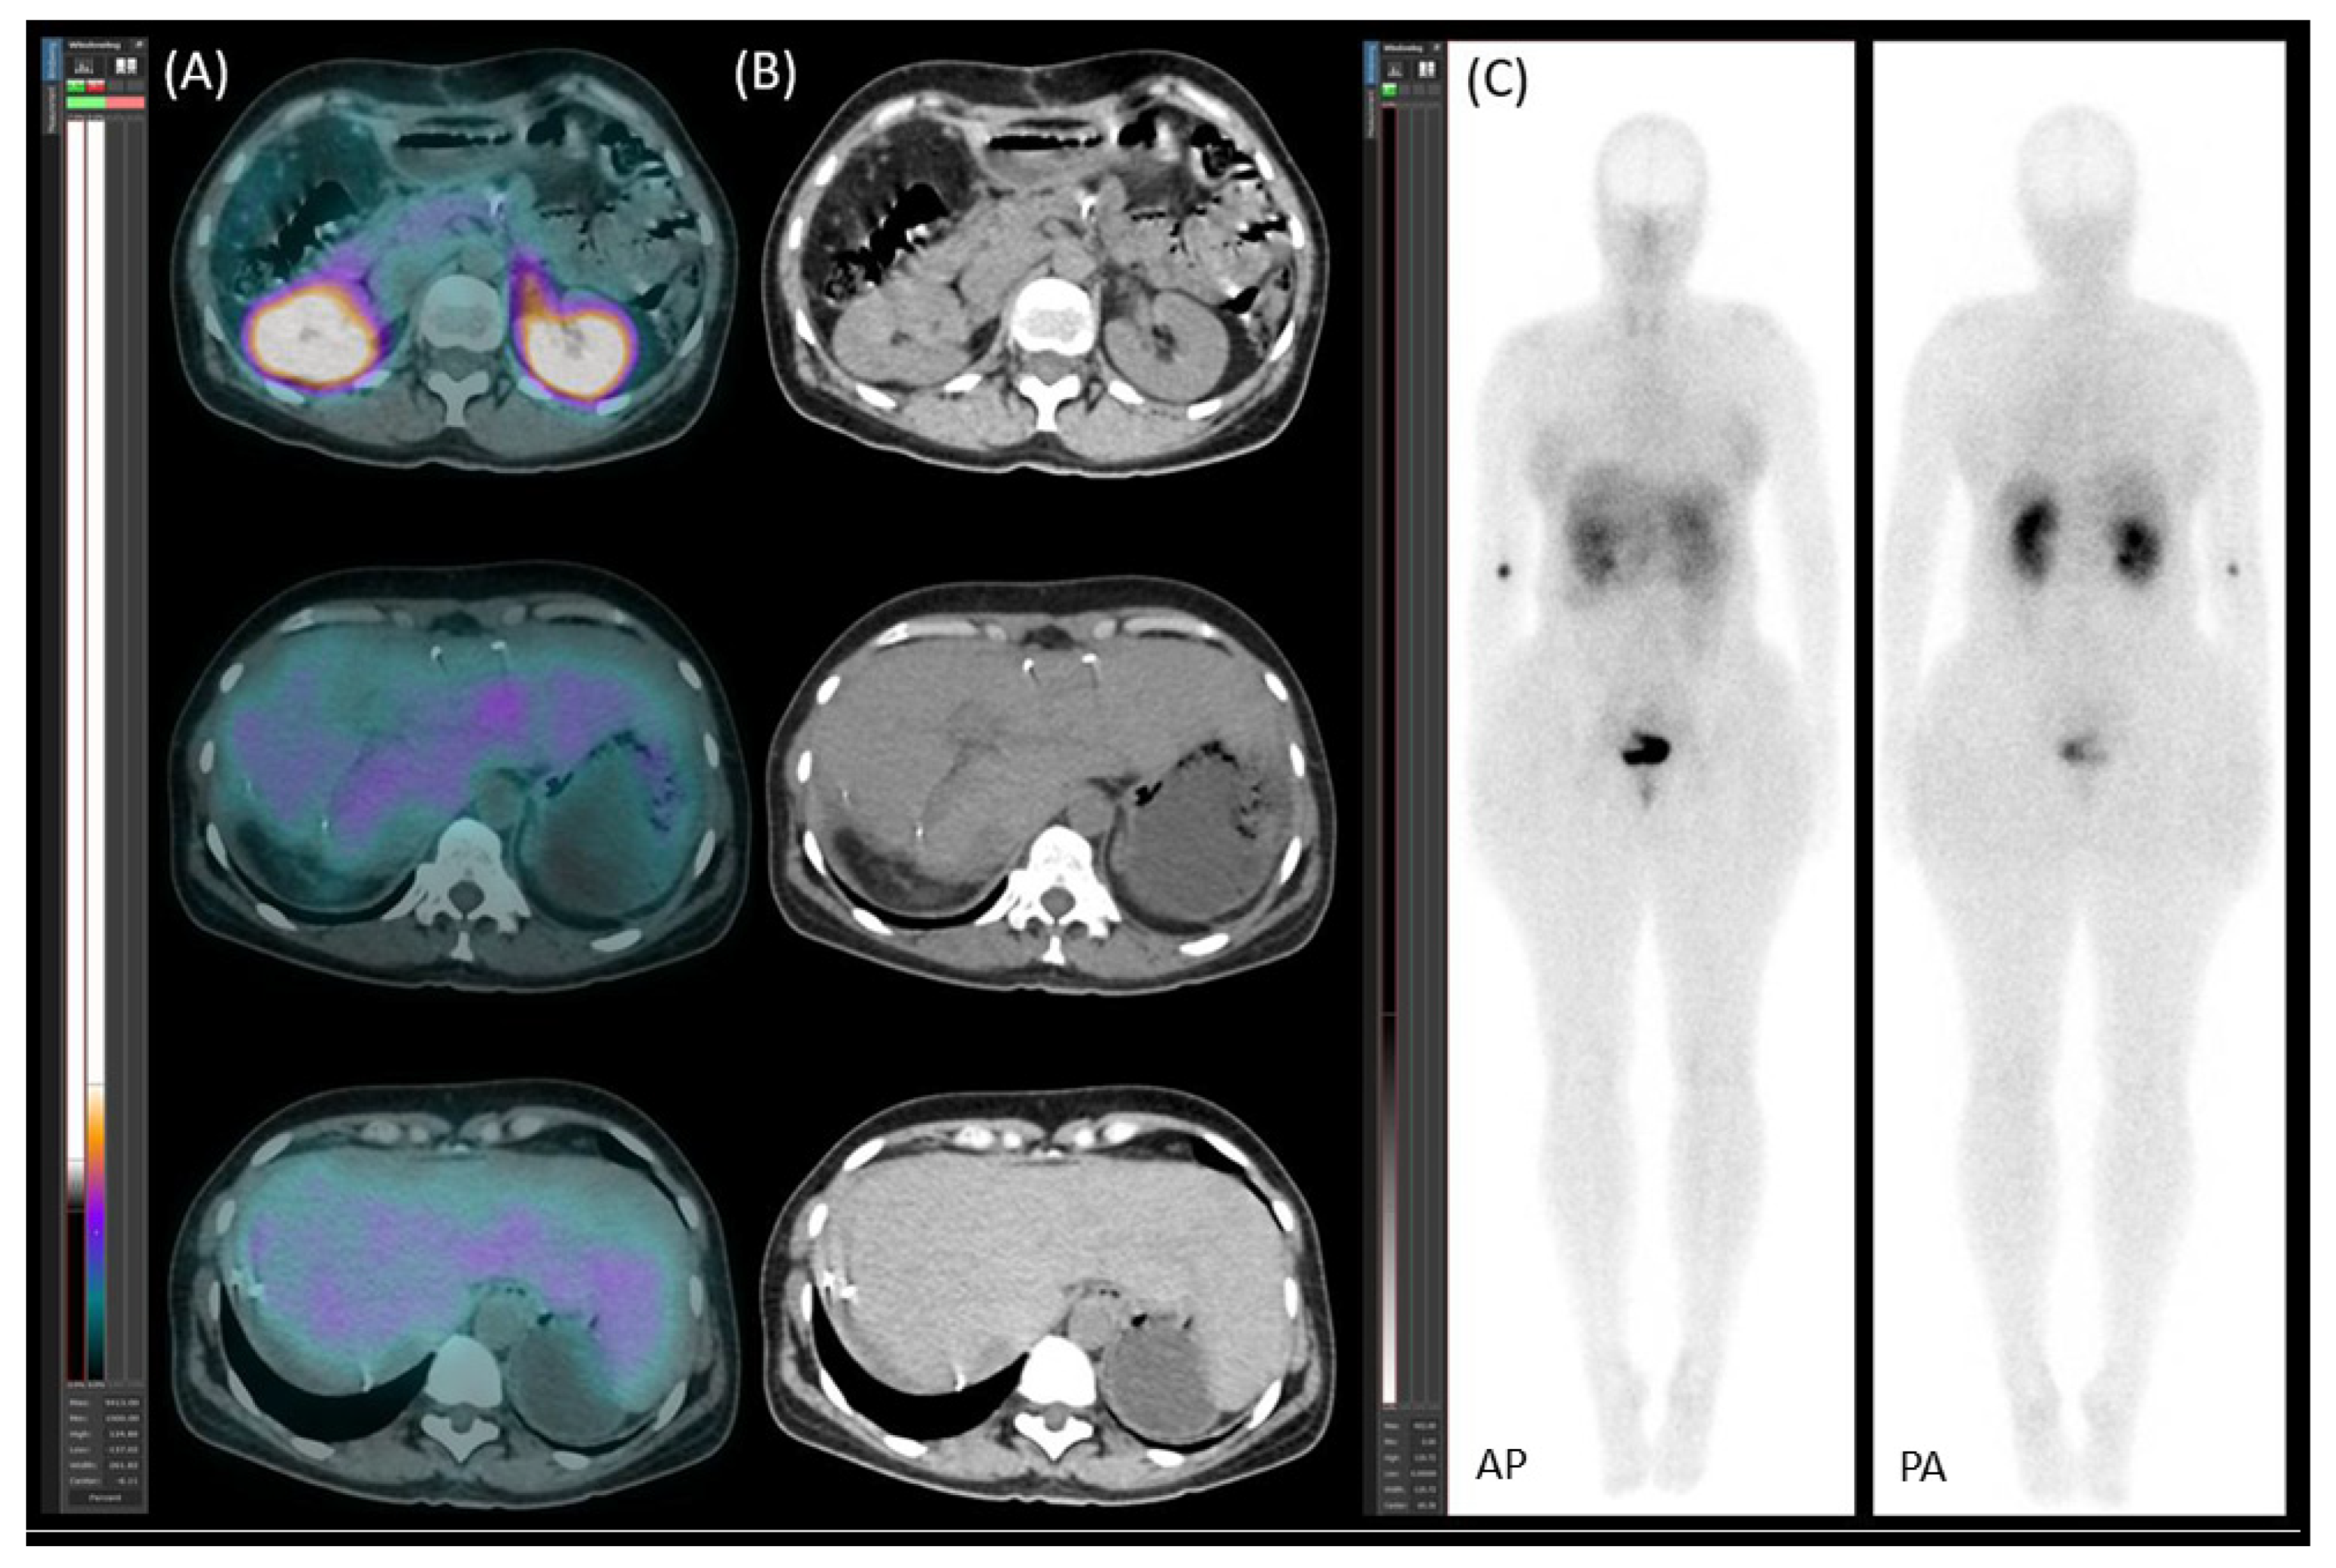

2.2. Preoperative Planning and First-Stage Surgery

2.3. Preoperative Planning and Second-Stage Surgery